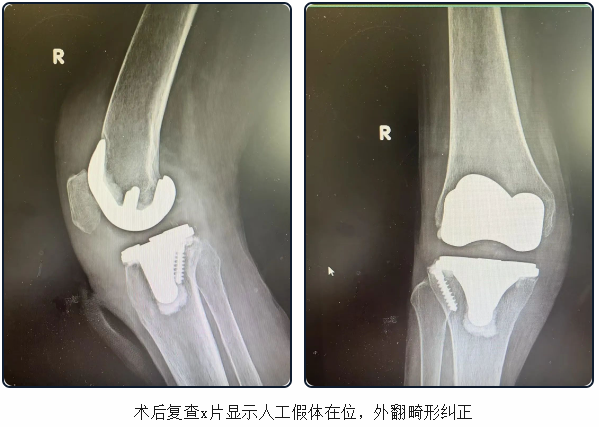

确定手术方案后,主刀医生、骨科主任医师夏炎带领团队经过2个多小时的紧张奋战,凭借精湛娴熟的专业技术与默契无间的协作配合,顺利完成了右侧全膝关节置换(微创)手术。术后2天,复查x片,假体在位,位置良好。